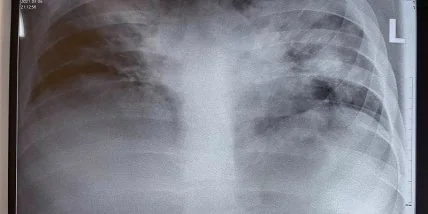

Она разместила фотографию снимка легких одного из молодых пациентов, у которого диагностировали коронавиурс. На изображении явно видны серые и черные пятна на органах воздушного дыхания.

Названы 4 группы людей, тяжело переносящих коронавирус"На фото - рентгенограмма 18-летнего молодого человека без явной сопутствующей патологии. Изменилось течение болезни, эффективность терапии, но мы также стараемся адаптировать наши подходы к лечению тяжёлых больных, исходя из новых условий", - отметила медик.